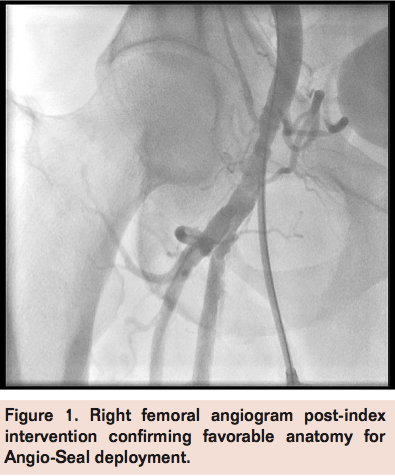

A 71-year-old male with history of coronary artery disease and 2 previous coronary artery bypass surgeries, hypertension, dyslipidemia, diabetes mellitus, and chronic kidney disease underwent successful bilateral renal artery stenting via the right femoral approach through an 8 Fr sheath in the setting of refractory hypertension and renal insufficiency. Following the procedure, an 8 Fr Angio-Seal (St. Jude Medical) vascular closure device was deployed without complications, after limited femoral angiogram confirmed favorable anatomy (Figure 1). He was discharged on dual antiplatelet therapy with aspirin 325 mg and clopidogrel 75 mg daily. One week following the procedure, the patient stated that he began having significant right lower extremity pain with minimal exertion, followed by intermittent right foot numbness despite compliance with all medications. However, the patient delayed any further evaluation until 2 weeks post-procedure, when the patient presented with right lower limb ischemia demonstrated by pallor and rest pain. Right groin ultrasound was suggestive of occlusive disease within the right common femoral artery. Ankle-brachial index was 0.3 on the right posterior tibial and 0.35 on the right dorsalis pedis. Due to the patient’s symptoms and abnormal non-invasive testing, right lower extremity angiography was offered.